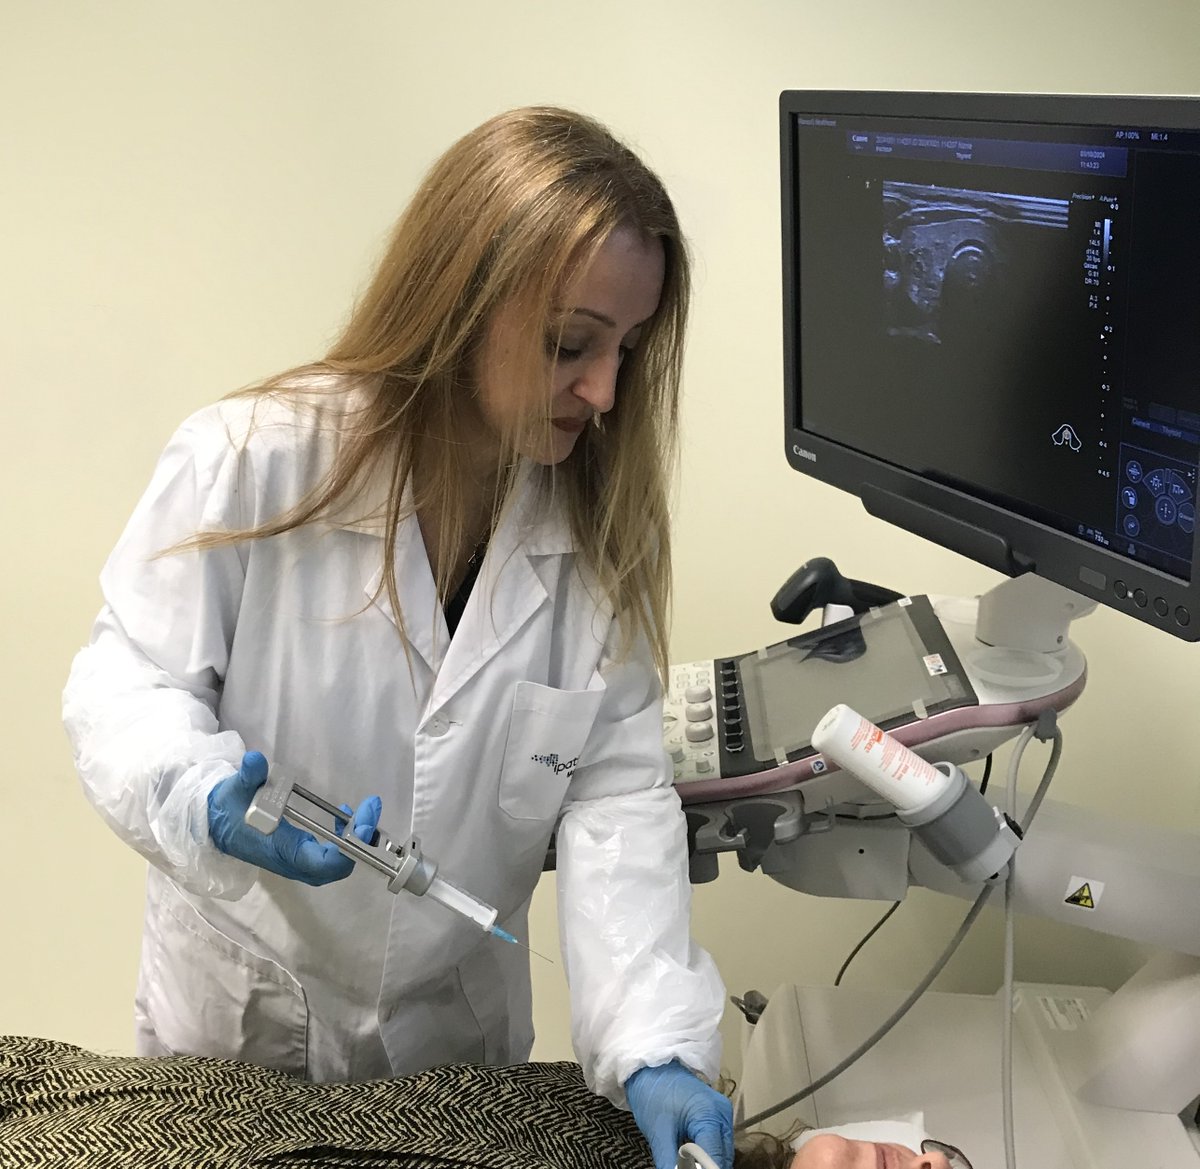

Very good conference in the European Society of Pathology (ESP) Meeting at #USCAP2023 by Catarina Eloy, MD,PhD It was pleasure see you again ☺️ Pic with Héctor-Enrique Torres-Rivas, MD an expert in Cytology and interventional cytology 💉